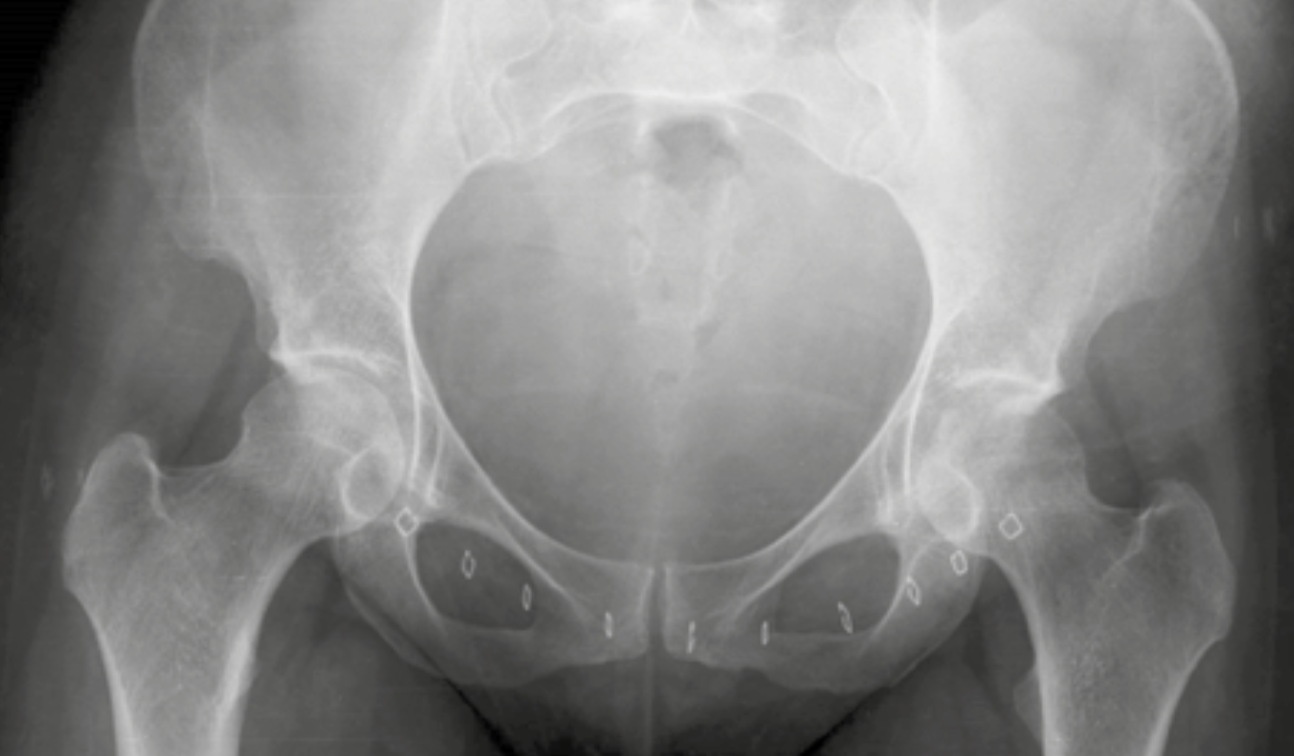

Coxite et sacroiliite bilatérale révélant une spondyloarthrite Figure 1